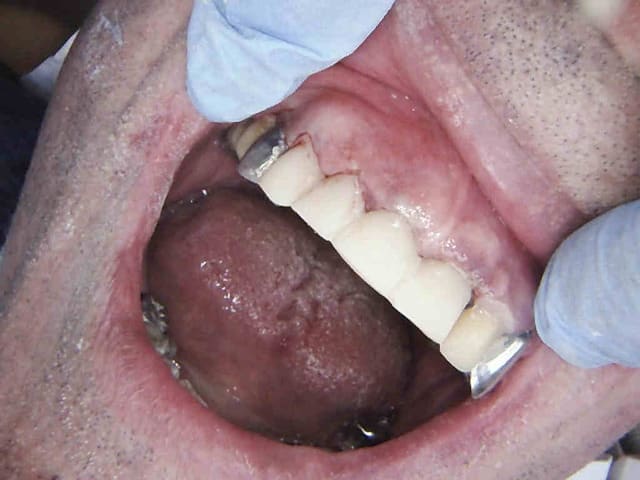

Endo taille empreinte provisoires 2H 30.

Avantage tu peux faire les provisoires et l'empreinte dans la séance et surtout tu peux raser les couronnes ce qui est un réel plus pour les endos surtout avec des pulpes rétractées comme ici ca évite de faire des conneries avec un abord palatin ou on ne voit rien du tout.